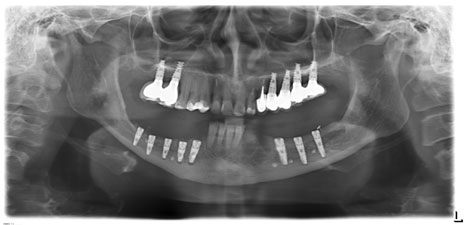

Латерализация и постеориоризация нижнечелюстного нерва

Пациентка C. 48 лет.

17, 16, 24, 25, 26, 27 – дентальные имплантаты, покрытые коронками;

37, 36, 35, 45, 46, 47 – отсутствуют;

С помощью Пьезотома проведена операция латерализации и постеориоризации нижнечелюстного нерва в области 35-37 и 45-47.

С помощью боров и костных конденсоров XiVE сформированы 7 лож имплантатов. Введены имплантаты XiVE в области 35, 36, 37 – D3,4/L13; 45, 46, 47 – D3,4/L9,5; 44 – D3,8/L9,5; 43 – D3,8/L11.

Костной крошкой заполнены дефекты в пришеечных областях имплантатов, уложен BIO OSS.

Сверху, перекрывая гребень, установлены барьерные мембраны Bio-Gide и фиксированы 6-ю мембранными гвоздями.